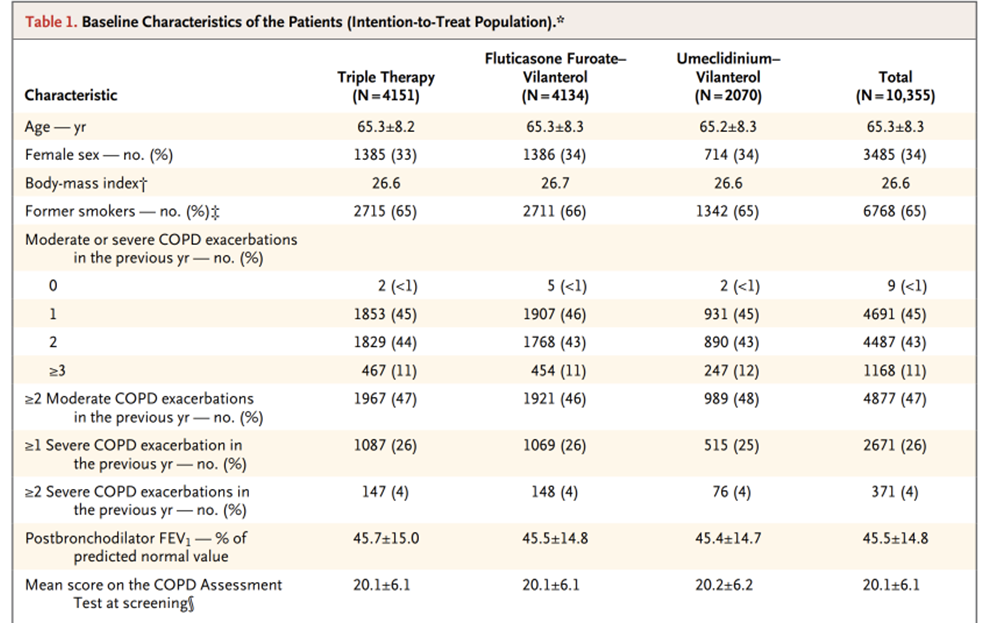

ただ今回のIMPACT試験に関して注目すべきはその”method”と”患者背景”です。

組み入れられているのは、

・40歳以上のCOPD患者

・CAT(COPD Assesment Test) 10点以上

・%1秒量:50%未満で少なくとも1回以上の中等症~重度のCOPD増悪歴が過去1年以内にある。

・%1秒量:50~80%で2回以上の中等症のCOPD増悪もしくは1回の重度のCOPD増悪が過去1年以内にある。

・ランダム化される2週間は元々の吸入薬を継続出来る。

とされています。

中等症の増悪:抗菌薬や全身ステロイド投与が必要であるが、外来で治療可能。

重症の増悪:入院が必要もしくは死亡症例。

それを元に組み入れられた患者数が10355人で、それらの患者背景がtable1にまとめられています。

先程のIMPACT試験では年齢の中央値が65.3歳で、BMIの中央値が26.6(!)

そこそこ若くて、体格がしっかりしたCOPD患者が対象になっているのです。その様な方々が少なくとも1年以内に1回は全身ステロイドが必要か入院する様な増悪をしているって普通にある事でしょうか。COPDだけでなく、喘息発作の要因も重なっているとも考えられるかもしれません。ICSを加える事が有利な結果になりそうですね。